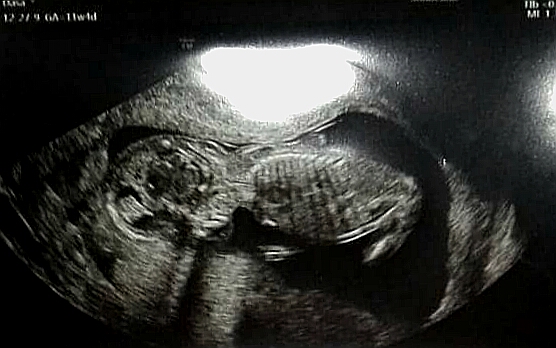

My máme za sebou kombinovaný test ktorý tentokrát dopadol dobre, začíname 15 tt